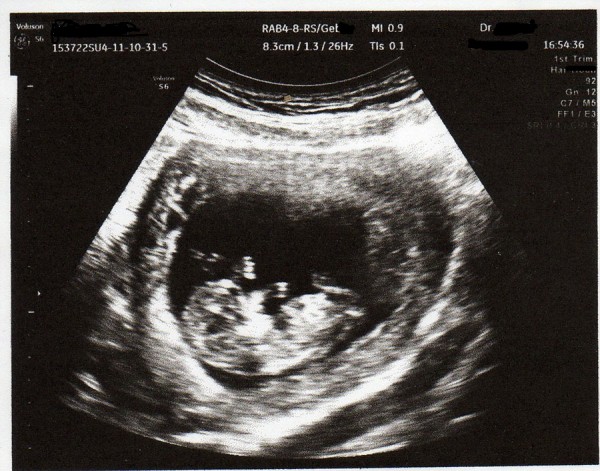

Die Entwicklung des Menschen ist doch auch Natur? Obwohl es eher das Wunder Mensch ist...

Hallo ChristasFotos,DSC04813_kl.jpg DSC05224_kl.jpg ich finde auch, die Entwicklung eines Menschen ist Natur pur. Aber denk dran, dass die Aufgabenstellung mindestens 3 Entwicklungsstadien wünscht.